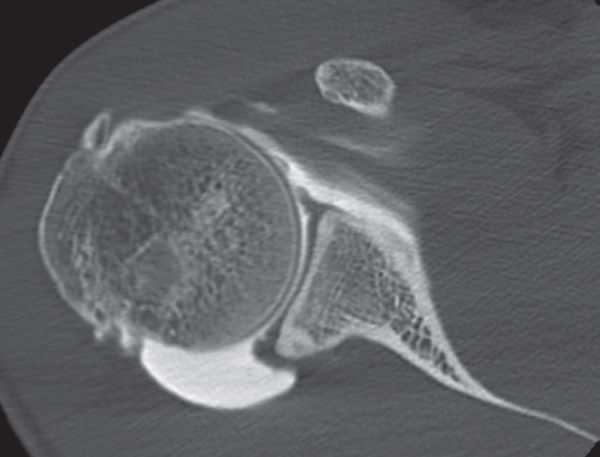

Computed tomography (CT) and magnetic resonance arthrography (MRA)

Examinations using intra-articular injection of a contrast medium (CT and MRA) are more reliable than simple MRI to visualize labral lesions and articular rotator cuff lesions (Figures).

Findings on computer tomography (CT).

Posterosuperior glenoidplasty described by Levigne et al. (Figures and Movie) seems to show good results for posterosuperior biomechanical impingement, when posterior osteophytes are clearly visible on the computed tomography (CT) scan.[48][49]

Treatment consists of a simple labral resection and liberal milling of the osteophytes and glenoid rim. This minimally invasive and risk-free technique seems very useful, with very good recovery rates at the same sporting level (73%). There are no major complications (notably osteoarthritis or secondary posterior instability at a mean follow-up of 49 months).[50]